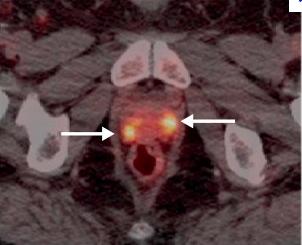

September 14, 2012 — The U.S. Food and Drug Administration (FDA) has approved the production and use of Choline C-11 injection, a positron emission tomography (PET) imaging agent used to help detect recurrent prostate cancer. Choline C-11 injection is administered intravenously to produce an image that helps to locate specific body sites for follow-up tissue sampling and testing in men with recurrent prostate cancer.

PET imaging with Choline C-11 injection is performed in patients whose blood prostate specific antigen (PSA) levels are increasing after earlier treatment for prostate cancer. An elevated PSA result suggests that prostate cancer may have returned, even though conventional imaging tests, such as computed tomography (CT), have not shown any signs of cancer. PET imaging is not a replacement for tissue sampling and testing.

The safety and effectiveness of Choline C-11 injection were verified by a systematic review of published study reports. Four independent studies examined a total of 98 patients with elevated blood PSA levels but no sign of recurrent prostate cancer on conventional imaging. After PET imaging with Choline C-11, the patients underwent tissue sampling of the abnormalities detected on the PET scans.

In each of the four studies, at least half the patients who had abnormalities detected on PET scans also had recurrent prostate cancer confirmed by tissue sampling of the abnormal areas. PET scan errors also were reported. Depending on the study, falsely positive PET scans were observed in 15 percent to 47 percent of the patients. These findings underscore the need for confirmatory tissue sampling of abnormalities detected with Choline C-11 injection PET scans. Aside from an uncommon, mild skin reaction at the injection site, no side effects to Choline C-11 injection were reported.